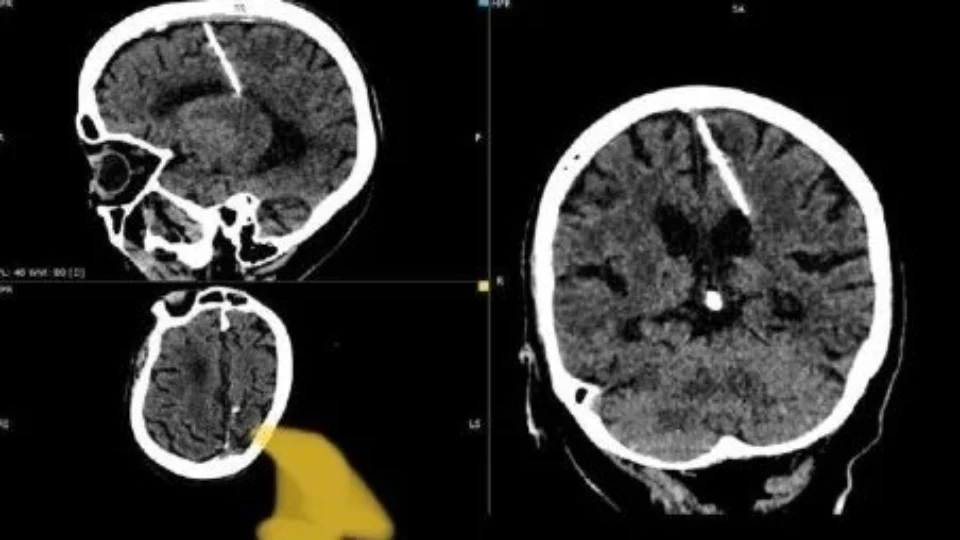

Uma idosa, de 80 anos, descobriu que convivia há décadas com uma agulha de 3 centímetros no cérebro.

O caso foi descoberto durante um exame de tomografia realizado por médicos na Rússia.

Os profissionais cogitam que a agulha, encontrada na cabeça da idosa, está com ela desde a infância.

Com o desenvolvimento da ‘moleira’ da criança, os ossos da cabeça foram se formado, deixando a agulha presa.